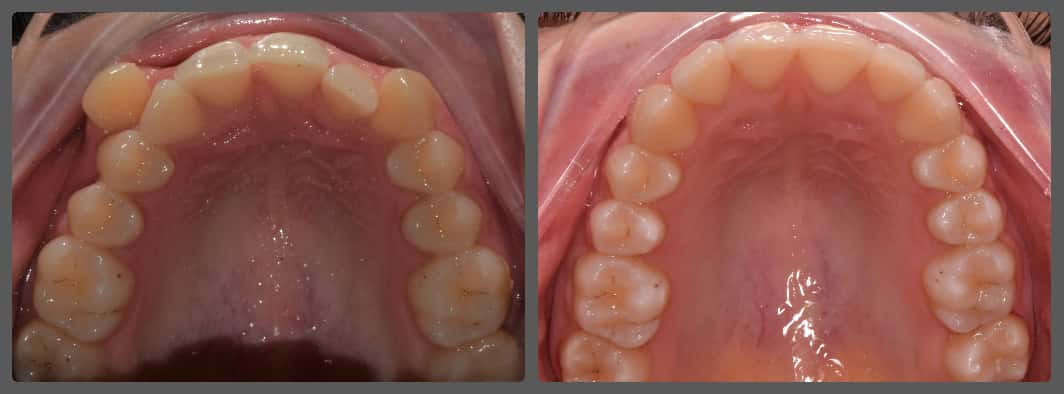

Bálint a 90 fokban elfordult jobb felső kismetszője miatt keresett meg engem. A vizsgálatokat követően kiderült, hogy a probléma ennél jóval komplexebb: súlyos keresztharapást, súlyos mélyharapást és felső rágósík billenést diagnosztizáltam nála. Alsó-felső H4 önligírozó fogszabályozó készülék, intermaxilláris gumihúzás és elülső harapásemelők segítségével korrigáltuk az eltéréseket. A bal oldali rágósík billenést fogszabályzási miniimplantátum alkalmazásával oldottuk meg. A bal felső-elülső fogakat felfelé mozgattuk, a miniimplantátumhoz húzva. Bálint esete igen komplex volt, ám kiváló együttműködésének köszönhetően 26 hónap alatt végeztünk a kezelésével (beleértve a 2-3 hónapos COVID-19 miatti leállást is). Az eredmény úgy gondolom magáért beszél!